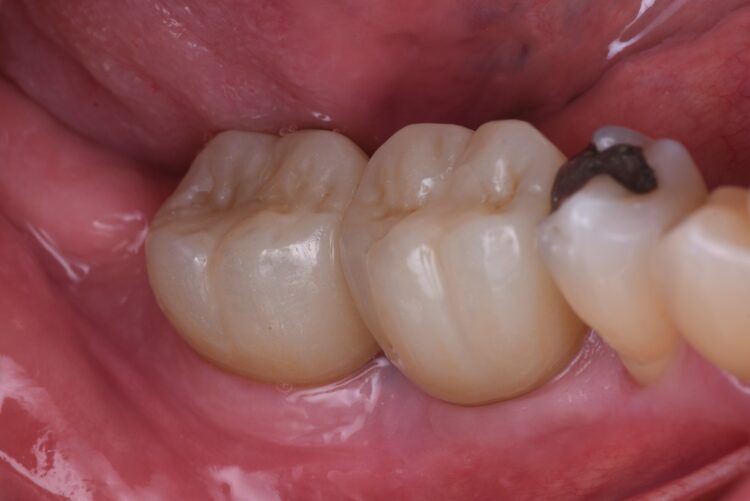

The implant crowns were constructed using custom-milled titanium abutments with a zirconia crown. Care was taken to ensure that any zirconia in contact with the tissues was polished rather than glazed to promote optimal soft tissue health. As seen in the post-treatment photos and x-rays, the hard and soft tissues have been well maintained, with excellent soft tissue thickness and a stable band of keratinised tissue achieved.

The immediate placement of the CONELOG® Progressive-Line implants in both molar sockets proceeded smoothly, achieving excellent primary stability. This approach not only preserved the existing bone and soft tissue but also provided a solid foundation for future prosthetic restoration. The use of MinerOss® Putty (allograft) played a crucial role in maintaining bone volume and soft tissue integrity, further contributing to the long-term success of the implants.